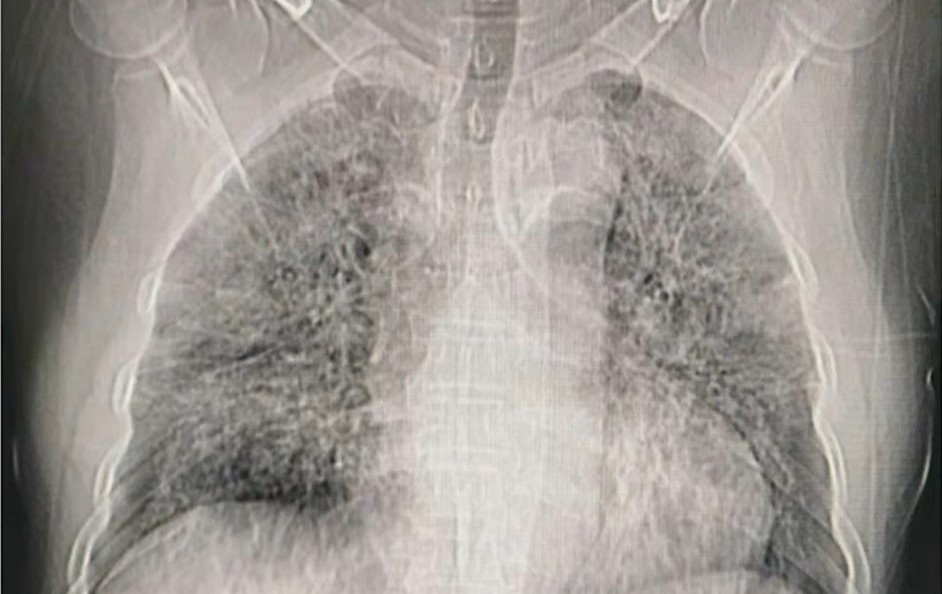

cách phát hiện người mắc covid 19

Vì sao nên dừng xét nghiệm nhanh Covid-19?

GS Nguyễn Anh Trí khẳng định hiện tại, nhiệm vụ số một là tìm virus SARS-CoV-2 trong cơ thể người nghi nhiễm. Xét nghiệm nhanh không đáp ứng được yêu cầu này.